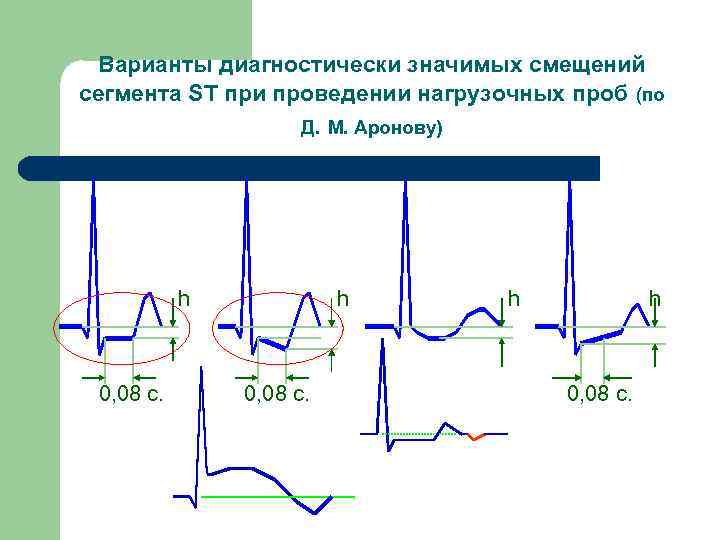

Варианты диагностически значимых смещений сегмента ST при проведении нагрузочных проб (по Д. М. Аронову) h 0, 08 c. h h 0, 08 c.